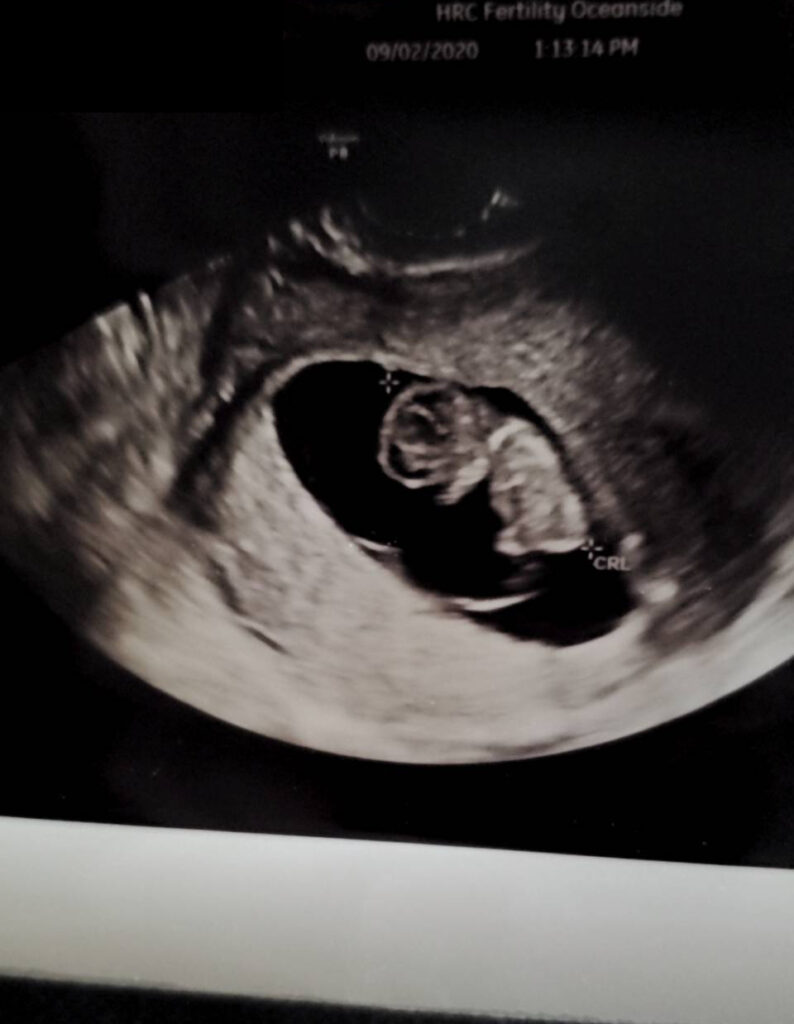

Baby超音波紀錄 : 10週 Posted on September 6, 2020 by yourtesttubebaby 十個禮拜大的小baby就是長的這樣的! 檢查一切平安! 祝福! ☀ 網站上每位小寶貝都是我們的成功案例,照片皆經父母親許可使用 ( 若未經允許請勿轉載 ) ☀ Posted in Uncategorized